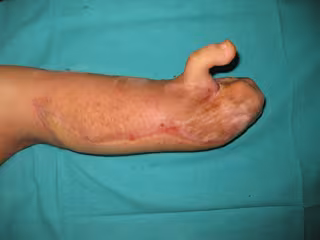

La colaboración entre los servicios de Cirugía Ortopédica y Traumatológica y Cirugía Plástica y Reconstructiva del Hospital General Universitario de Alicante ha permitido la intervención quirúrgica de una niña de 12 años, que ha recuperado la capacidad funcional de la mano tras haberle practicado una doble reconstrucción con un colgajo libre de la pierna y la transferencia combinada de un dedo del pie a la mano para la restitución del pulgar, según ha informado en un comunicado la Generarlitat.

Es la primera intervención de estas características que se practica en la Comunitat Valenciana y que ha requerido de técnicas de microcirugía para la conexión de arterias, venas y nervios de la muñeca en el primer colgajo fasciocutáneo y, técnicas de ultramicrocirugía para los vasos del dedo del pie hacia el colgajo transferido en primer lugar. Actualmente, la paciente, que ha sido dada de alta, se encuentra en periodo de rehabilitación de su mano y evoluciona satisfactoriamente.

La paciente, de 12 años, había sufrido una grave quemadura a los pocos meses de vida que le causó la pérdida todos los dedos de esa mano. "La retracción cutánea provocada tras un largo periodo de curas había originado una dorsiflexión completa de la muñeca, provocando que por un complejo proceso de volteo, la palma de la mano se encontrara incluida en el tercio medio del antebrazo", explican los especialistas que han participado en la operación.

Mediante la microcirugía se han podido transferir dos tipos de tejidos: uno de piel y grasa de la pierna de gran tamaño diseñado para reponer la gran pérdida de sustancia originada tras la colocación de la mano en su posición anatómica y por otro lado, el transplante de un dedo del pie para reconstruir la función de pinza del pulgar.